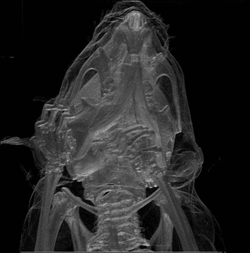

Micro-CT

Principle: Computed Tomography (CT) imaging works through X-rays that are emitted from a focused radiation source that is rotated around the test subject placed in the middle of the CT scanner.[2] The X-ray is attenuated at different rates depending on the density of tissue it is passing through, and is then picked up by sensors on the opposite end of the CT scanner from the emission source. In contrast to traditional 2D X-ray, since the emission source in a CT scanner is rotated around the animal, a series of 2D images can then be combined into 3D structures by the computer.

Strengths: Micro-CT can have excellent spatial resolution, which can be up to 6 µm when combined with contrast agents. However, the radiation dose needed to achieve this resolution is lethal to small animals, and a 50 µm spatial resolution is a better representation of the limits of micro-CT. It is also decent in terms of image acquisition times, which can be in the range of minutes for small animals.[10] In addition, micro-CT is excellent for bone imaging.

Weaknesses: One of the major drawbacks of micro-CT is the radiation dosage placed on test animals. Although this is generally not lethal, the radiation is high enough to affect the immune system and other biological pathways, which may ultimately change experimental outcomes.[13] Also, radiation may affect tumor size in cancer models as it mimics radiotherapy, and thus extra control groups might be needed to account for this potential confounding variable. In addition, the contrast resolution of micro-CT is quite poor, and thus it is unsuitable for distinguishing between similar tissue types, such as normal vs. diseased tissues.

Cancer research: Micro-CT is most often used as an anatomical imaging system in animal research because of the benefits that were mentioned earlier. Contrast agents can also be injected to study blood flow. However, contrast agents for micro-CT, such as iodine, are difficult to conjugate molecular targets1 with, and thus it is rarely used in molecular imaging techniques. As such, micro-CT is often combined with micro-PET/SPECT for anatomical and molecular imaging in research.[14]